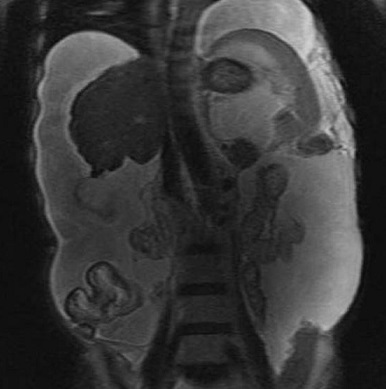

Image IRM de la cirrhose du foie : Cette

. Morphologie de la cirhose du foie sur IRM est

resemble que dans le CT et echographie . Aspect

radiologique IRM en T1 de cirrhose du foie est image

isosignal a bord et parenchyme irregulie

nodulaire et a hyposignal en T2 .

Image radiologique IRM du

foie en T2 coupe axiale : Foie a petite taille a

bord irregulier avec hypertension portal ,

splenomegalie et ascite important |

Image en coupe coronale |